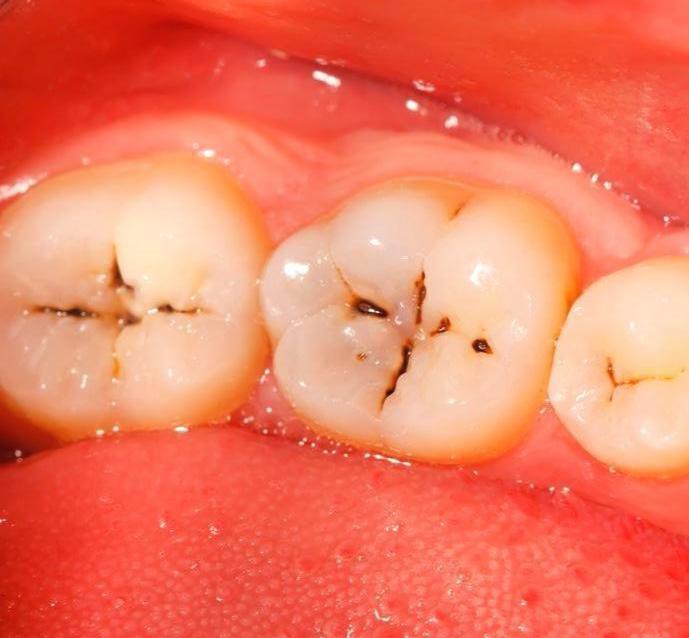

这是一种龋齿,窝沟龋。

龋齿按不同的牙齿部位可以分为窝沟龋和平滑面龋。

我们的前磨牙和磨牙咬合面是窝状的,上面有很多沟隙,它们被称为“窝沟”。这种窝沟可以使口腔咬合面凹凸不平,增大咀嚼面积,提高咀嚼效率。

但这个窝沟有一个缺点,那就是容易使食物、菌斑滞留在这里,并且不易清洁,因此窝沟是龋齿最容易发生的部位。

窝沟龋早期的表现就是后牙咬合面有黑线

但如果不加以重视龋坏会扩散,就会沿着釉柱方向发展而加深,达到牙本质而形成一个口小底大的三角形,然后沿牙本质界扩散。

另外,由于釉质在窝沟底部牙厚度较薄,窝沟龋很容易进展到牙本质,造成大面积的牙齿病变,所以窝沟龋病程发展很快,程度也会比其他口腔疾病更严重。除此之外,细菌还可以通过牙本质小管到达牙髓腔,引发炎症。